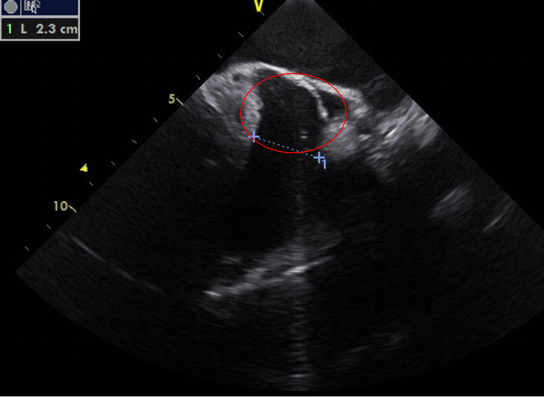

超声心动图在MR介入术中起着不可或缺的作用,下面以目前最为成熟的经导管二尖瓣夹合术MitralClip为例,阐述MR介入术中的超声评价。MitralClip是在经食管超声心动图实时监测和引导下的操作,所有的导管操作由经食管超声心动图监测和引导[17]。经食超声心动图首先引导房间隔穿刺,使得房间隔穿刺点距二尖瓣瓣环平面的高度为3.5~4.0 cm(图12)。之后,经食管超声心动图引导输送系统进入左心房并调弯、顶端垂直指向二尖瓣口。接着,经食管超声心动图引导夹合器在二尖瓣上方定位、夹合器进入左心室、引导夹合器捕获和夹合瓣膜。夹合器捕获瓣膜位置,应该位于彩色多普勒显示反流束最大处。在整个手术过程中,两个超声视野非常重要,为手术的工作切面,其中X-plane双切面,包括三腔心切面(左心室长轴切面)及二尖瓣交界处二腔心切面(图13)。三腔心切面可以显示二尖瓣A2、P2的位置,捕获瓣膜前二尖瓣夹合器应该在这个切面显示为V字形,此时瓣夹合器臂与二尖瓣开放线垂直,分别位于A2、P2的位置,在该切面通过调整夹合器位置可使得夹合器更靠近前叶或后叶;二尖瓣交界处二腔心切面显示P1、A2、P3,捕获瓣膜前二尖瓣夹合器在该平面应该为直线形,在该切面通过调整夹合器位置可使得夹合器更靠近瓣环内交界(P3或A3)或外交界(P1或A1)。另外一个工作切面为三维超声心动图的“二尖瓣外科视野”,可以整体观察夹合器的位置、臂指向的方向(图14)。目前有限经验显示,经心尖二尖瓣夹合术(ValveClamp)术中超声心动图指导和MitralClip总体上类似,但仍有部分差异,其超声心动图规范尚在探索中。

注:LA,左心房;LV,左心室;RA,右心房;RV,右心室

图 12 经食管超声心动图食管中段的四腔心切面,显示房间隔穿刺平面距二尖瓣瓣环平面的高度(箭头所示)